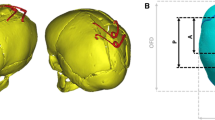

Partial least squares analysis of anterior–posterior craniotomy size (AP). a Correlation between PLS AP shape vector and surgical parameter AP showing a strong association. b 3D, lateral and top views of computed template shape deformed along the PLS AP shape mode for small and big values of AP (±3 SD), showing that big values of AP are associated with bigger bi-parietal widening

AP accounted for \(11\%\) of the shape response. As shown in Fig. 4a, AP and its PLS shape vector were significantly correlated (\(n=19\), Pearson’s \(r=0.64, p=0.002\)). Small values of AP were associated with bullet-like post-removal head shapes (wider anteriorly than posteriorly) with a prominence on top of the head, whereas big AP values were related to bigger bi-parietal widening (Fig. 4b), focused more centrally and posteriorly.